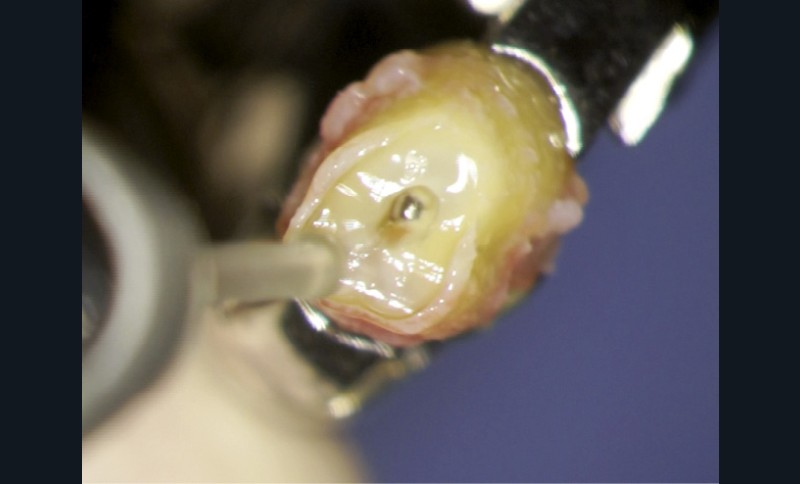

Coiffages pulpaires

L’exposition pulpaire a deux causes principales : traumatique ou carieuse.

Dans le cas d’un traumatisme récent, chez le jeune ou l’adulte, la pulpe doit être systématiquement coiffée pour conserver la vitalité pulpaire

Concernant les coiffages sur dents adultes, un bon diagnostic doit être posé pour faire le bon choix entre la conservation pulpaire totale, partielle ou le traitement endodontique [34]. Il est particulièrement indiqué chez le jeune dont les dents immatures ont une édification apicale incomplète.

Plusieurs facteurs interviennent dans le bon pronostic du coiffage pulpaire : l’élimination de l’inflammation, le contrôle de l’infection et la biocompatibilité des matériaux utilisés [35].

Le laser Er:YAG va permettre une élimination des débris en surface, une stérilisation, avec comme irrigation de l’eau stérile [36] et en coupant le spray, une hémostase avec la formation d’une couche de coagulation [37] propre à la formation d’un pont dentinaire au contact du biomatériau, qui peut être bio-actif, tel que la Biodentine (Septodont) (fig. 6a à d).

Protocole opératoire : sous anesthésie, une cavité suffisante à recevoir le biomatériau (2 à 3 mm) sous champ opératoire est réalisée. La désinfection au laser Er:YAG (40 mJ ; 20 Hz) sous spray, pendant 20 secondes, est alors mise en œuvre. S’en suit éventuellement une coagulation de 3 secondes, en coupant le spray, puis la mise en place du biomatériau Biodentine (Septodont). Il sera ensuite recouvert d’un matériau de restauration adéquate.